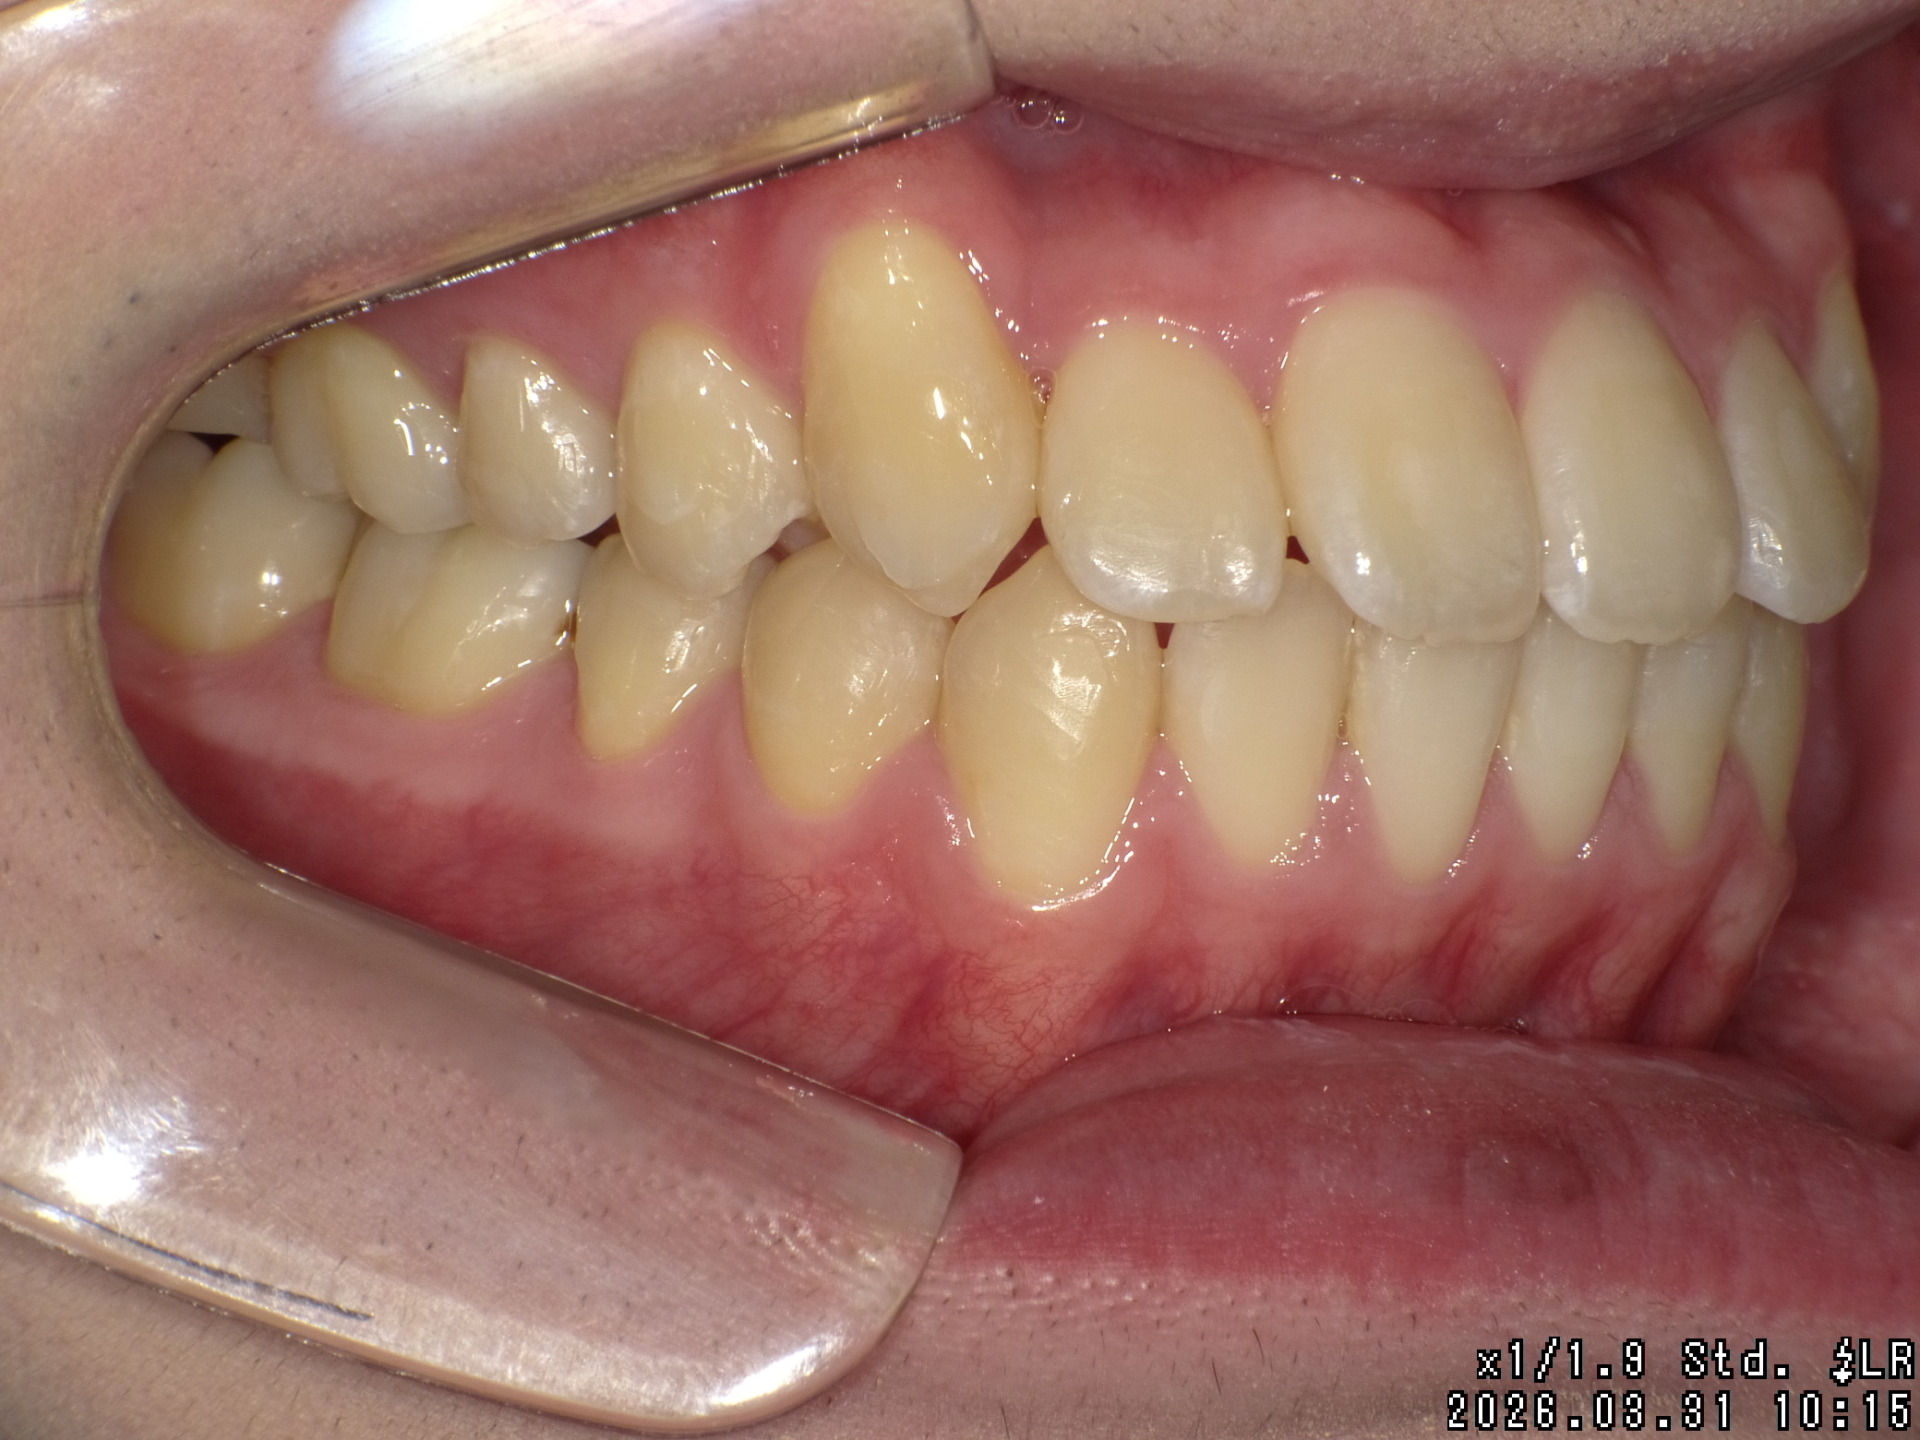

After